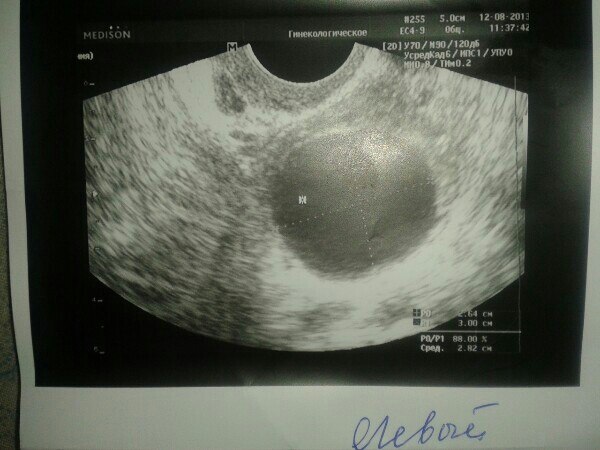

Девчоки. Я в мае перенесла лапару на поликистоз. В прошлом месяце в пр.яичнике были 2 фоллика, из которых 1 перерос. В левом ничего не было((( Вчера на 10ДЦ на узи врач увидела вот такую картину. в правом киста, а в левом переросший фоллик. И опять не назначила мне укол ХГЧ для стимуляции. Сказала прийти к ним на узи на 3-5 ДЦ в след.цикле. А сегодня появилась боль в районе правого яичника. Девочки, я уже отчаилась. Так жутко на сердце((( Неужели я не смогу забеременеть.